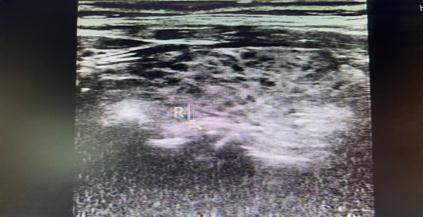

桥本氏甲状腺炎:甲状腺大小可正常,也可以呈非均匀性肿大,不过在疾病后期一般都表现为甲状腺缩小。超声图像一般分为弥漫型、局限型和结节形成型。其中结节形成型有时候经常会在体检时发现为结节而来就诊,有时候较难与恶性结节相鉴别,可以定期复查,或者超声造影或者进行结节穿刺进行进一步检查。

图片